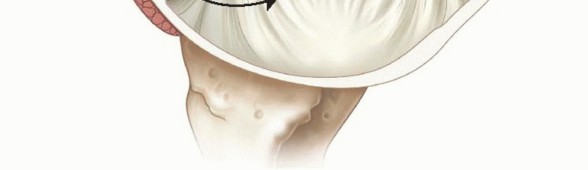

Illustration of inferior glenohumeral ligament - Dr. Mohammed Hutaif

The capsuloligamentous structures serve as the primary static restraints of the shoulder. The most critical of these is the Inferior Glenohumeral Ligament (IGHL) complex. Composed of a distinct anterior band, a posterior band, and an intervening axillary pouch, the IGHL functions as a reciprocal hammock. In the provocative position of abduction and external rotation, the anterior band becomes taut, acting as the primary restraint to anterior translation.

Image

The superior and middle glenohumeral ligaments play secondary, yet important, roles. The SGHL primarily resists inferior translation in adduction, while the MGHL resists anterior translation in the mid-ranges of elevation. The labrum itself not only deepens the socket but serves as the robust, continuous attachment site for these ligaments. Disruption of this labral-ligamentous complex destroys the joint's negative intra-articular pressure (the "suction cup" effect) and allows obligate, pathologic translation of the humeral head.